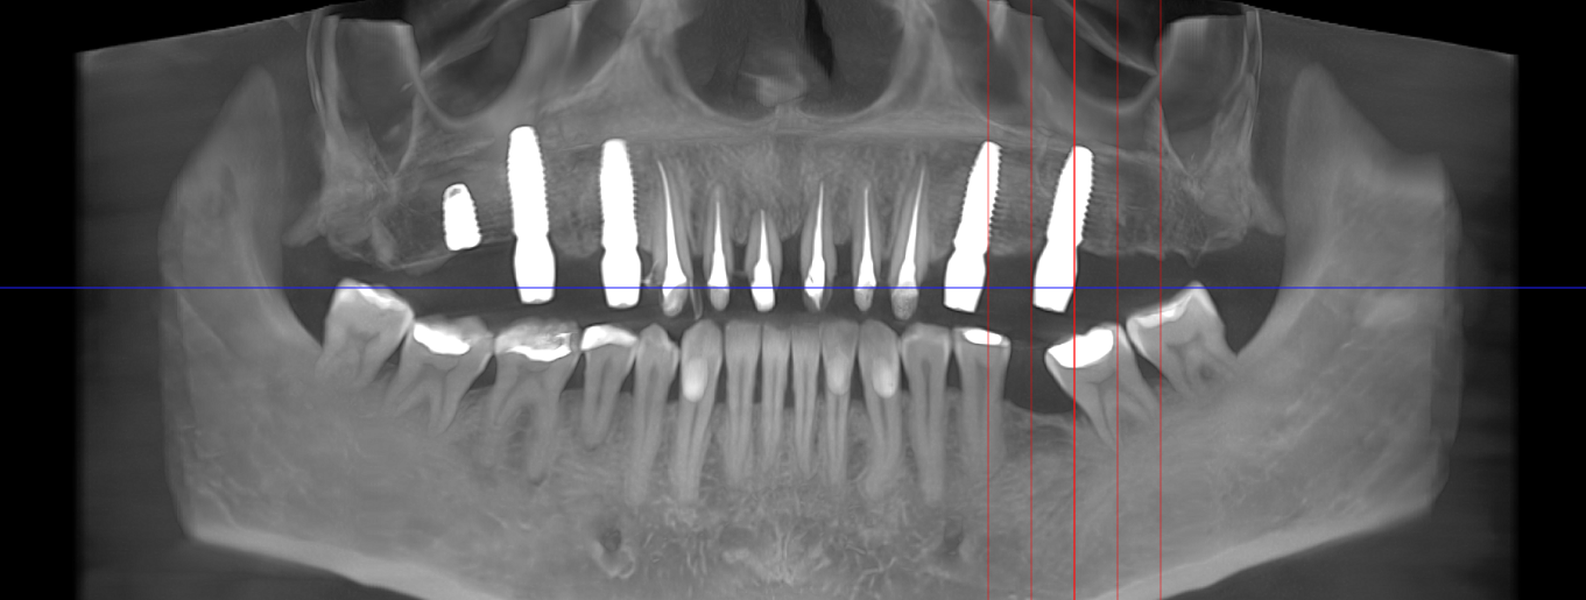

Reabilitarea complexă în stomatologie presupune refacerea completă a sistemului dentoalveolar, atât din punct de vedere funcțional, cât și estetic. Procesul începe cu o examinare detaliată a cavității bucale, interpretarea investigațiilor imagistice (CBCT), evaluarea musculaturii, articulațiilor temporomandibulare și a parametrilor estetici.

Tomografii (CBCT)

Caz 1